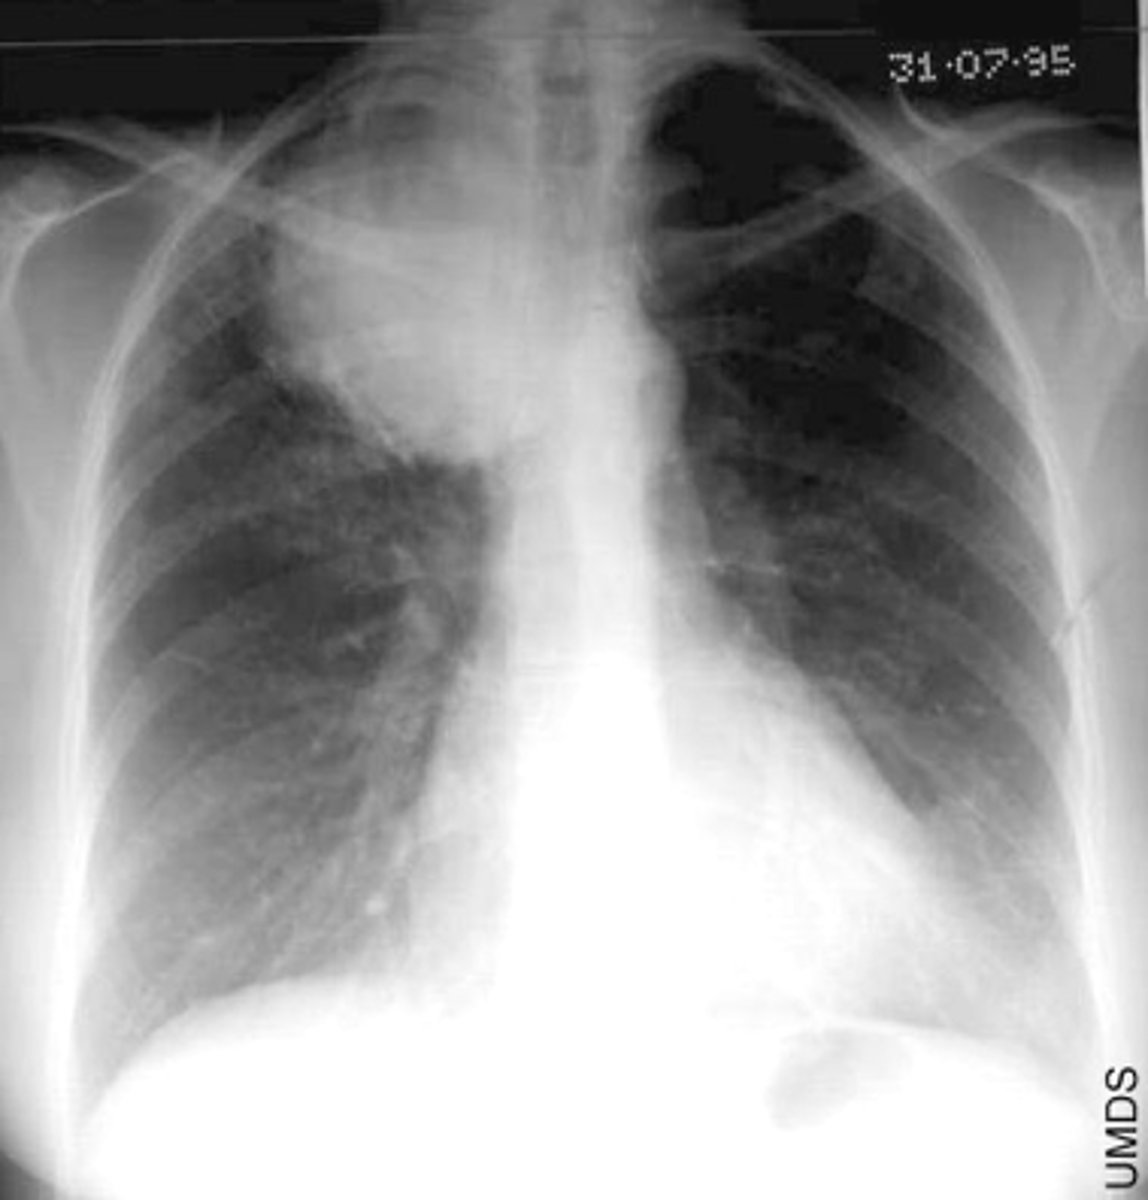

CAP- interstitial